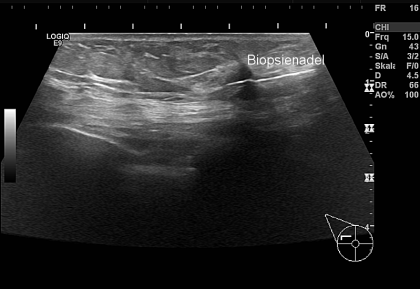

Biopsie eines 5 mm kleinen Mammacarcinoms

Hier sehen sie einen verdächtigen Knoten in der rechten Brust von 5 mm Durchmesser im hochauflösenden Ultraschall. Es mussgeklärt werden, ob dieser Tumor bösartig ist, um welchen Tumortyp es sich handelt und ob an der Zelloberfläche Hormonrezeptoren vorhanden sind.

Zunächst wird die Biopsienadel unter Ultraschallkontrolle an den Tumor herangeführt